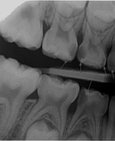

Součástí preventivní prohlídky u zubního lékaře je klinické vyšetření zaměřené na dobré prořezávání zubů, správný vývoj čelistí, zlozvyky a včasné nalezení případných defektů. Po uzavření mezizubních mezer má docházet i rentgenologické vyšetření v podobě dvou malých snímků (tzv. bite-wing) zaměřené na včasné vyhledání mezizubních kazů. Ty jsou na povrchu zubů pozorovatelné až v pozdějším stádiu. Přibližně v osmi letech se standardně zhotovuje i snímek OPG, na němž jsou vidět obě čelisti včetně zárodků stálých zubů.

Rozsáhlé kazy na dočasných stoličkách